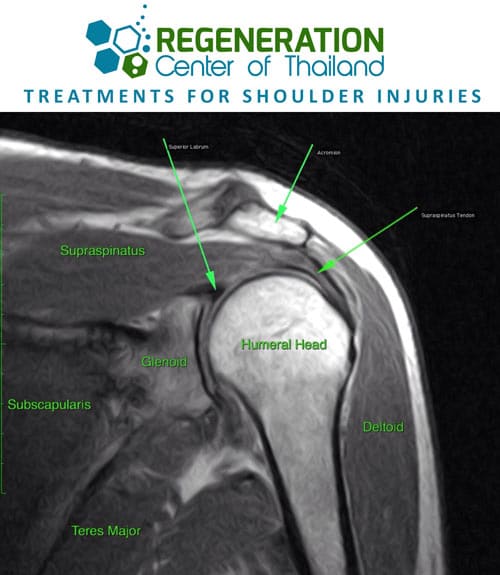

Our shoulder is one of the most complex and versatile socket + ball joint systems in the human body. The socket and joint connections are quite shallow however and require the assistance of four tendons that are collectively known as the Rotator Cuff keep the ball firmly inside the socket during physical rotations and any lifting of weights. The shoulders’ are constantly being put through extensive wear and tear that can sometimes lead to injuries and chronic pain.

Unfortunately, these injuries are also some of the most difficult areas to repair surgically. It is estimated that nearly 60% of all Arthroscopic shoulder surgeries fail to heal properly, resulting in a weak range of motion and lack of strength leading to a high risk of injury by “retears” in the tendon. What’s important to note here is that the main reason the shoulders did not heal naturally was due to our bodies inability to use paracrine cell communication to recruit our bodies circulating stem cells to the shoulder to begin the natural cell restoration cycle.